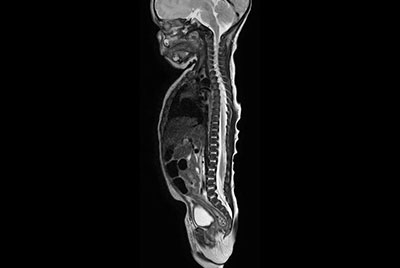

Fetal Brain and Spine